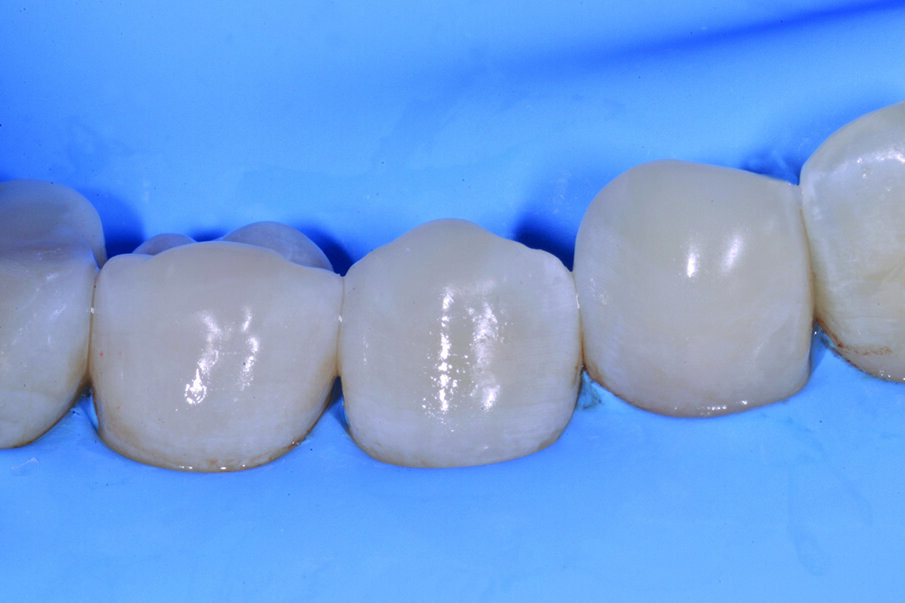

Figg. 2-5_Rimozione dei vecchi restauri presenti su 4.6 e 4.7: gli elementi vengono restaurati con tecnica diretta utilizzando dentina e smalto Enamel Plus HRI Bio Function.

Figg. 6-9_Le superfici occlusali erose e/o abrase vengono ricostruite con strati sottili di smalto composito Enamel Plus HRi Bio Function.